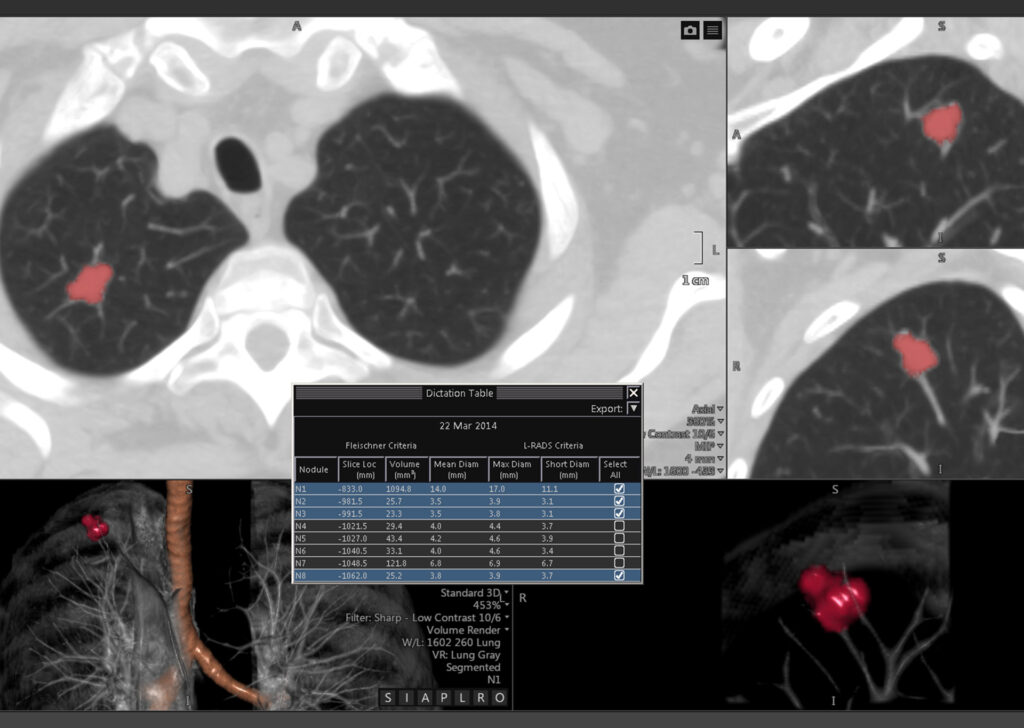

CT Lung Analysis

CT Lung Analysis aids in measuring and characterizing lung nodules. The interface and automated tools help to efficiently determine growth patterns and compose comparative reviews.

Visia™ CT Lung CAD

Visia CT Lung CAD is integrated into Vitrea® Advanced Visualization and facilitates time-efficient and safe radiological diagnosis of MSCT-images in clinical daily routine.